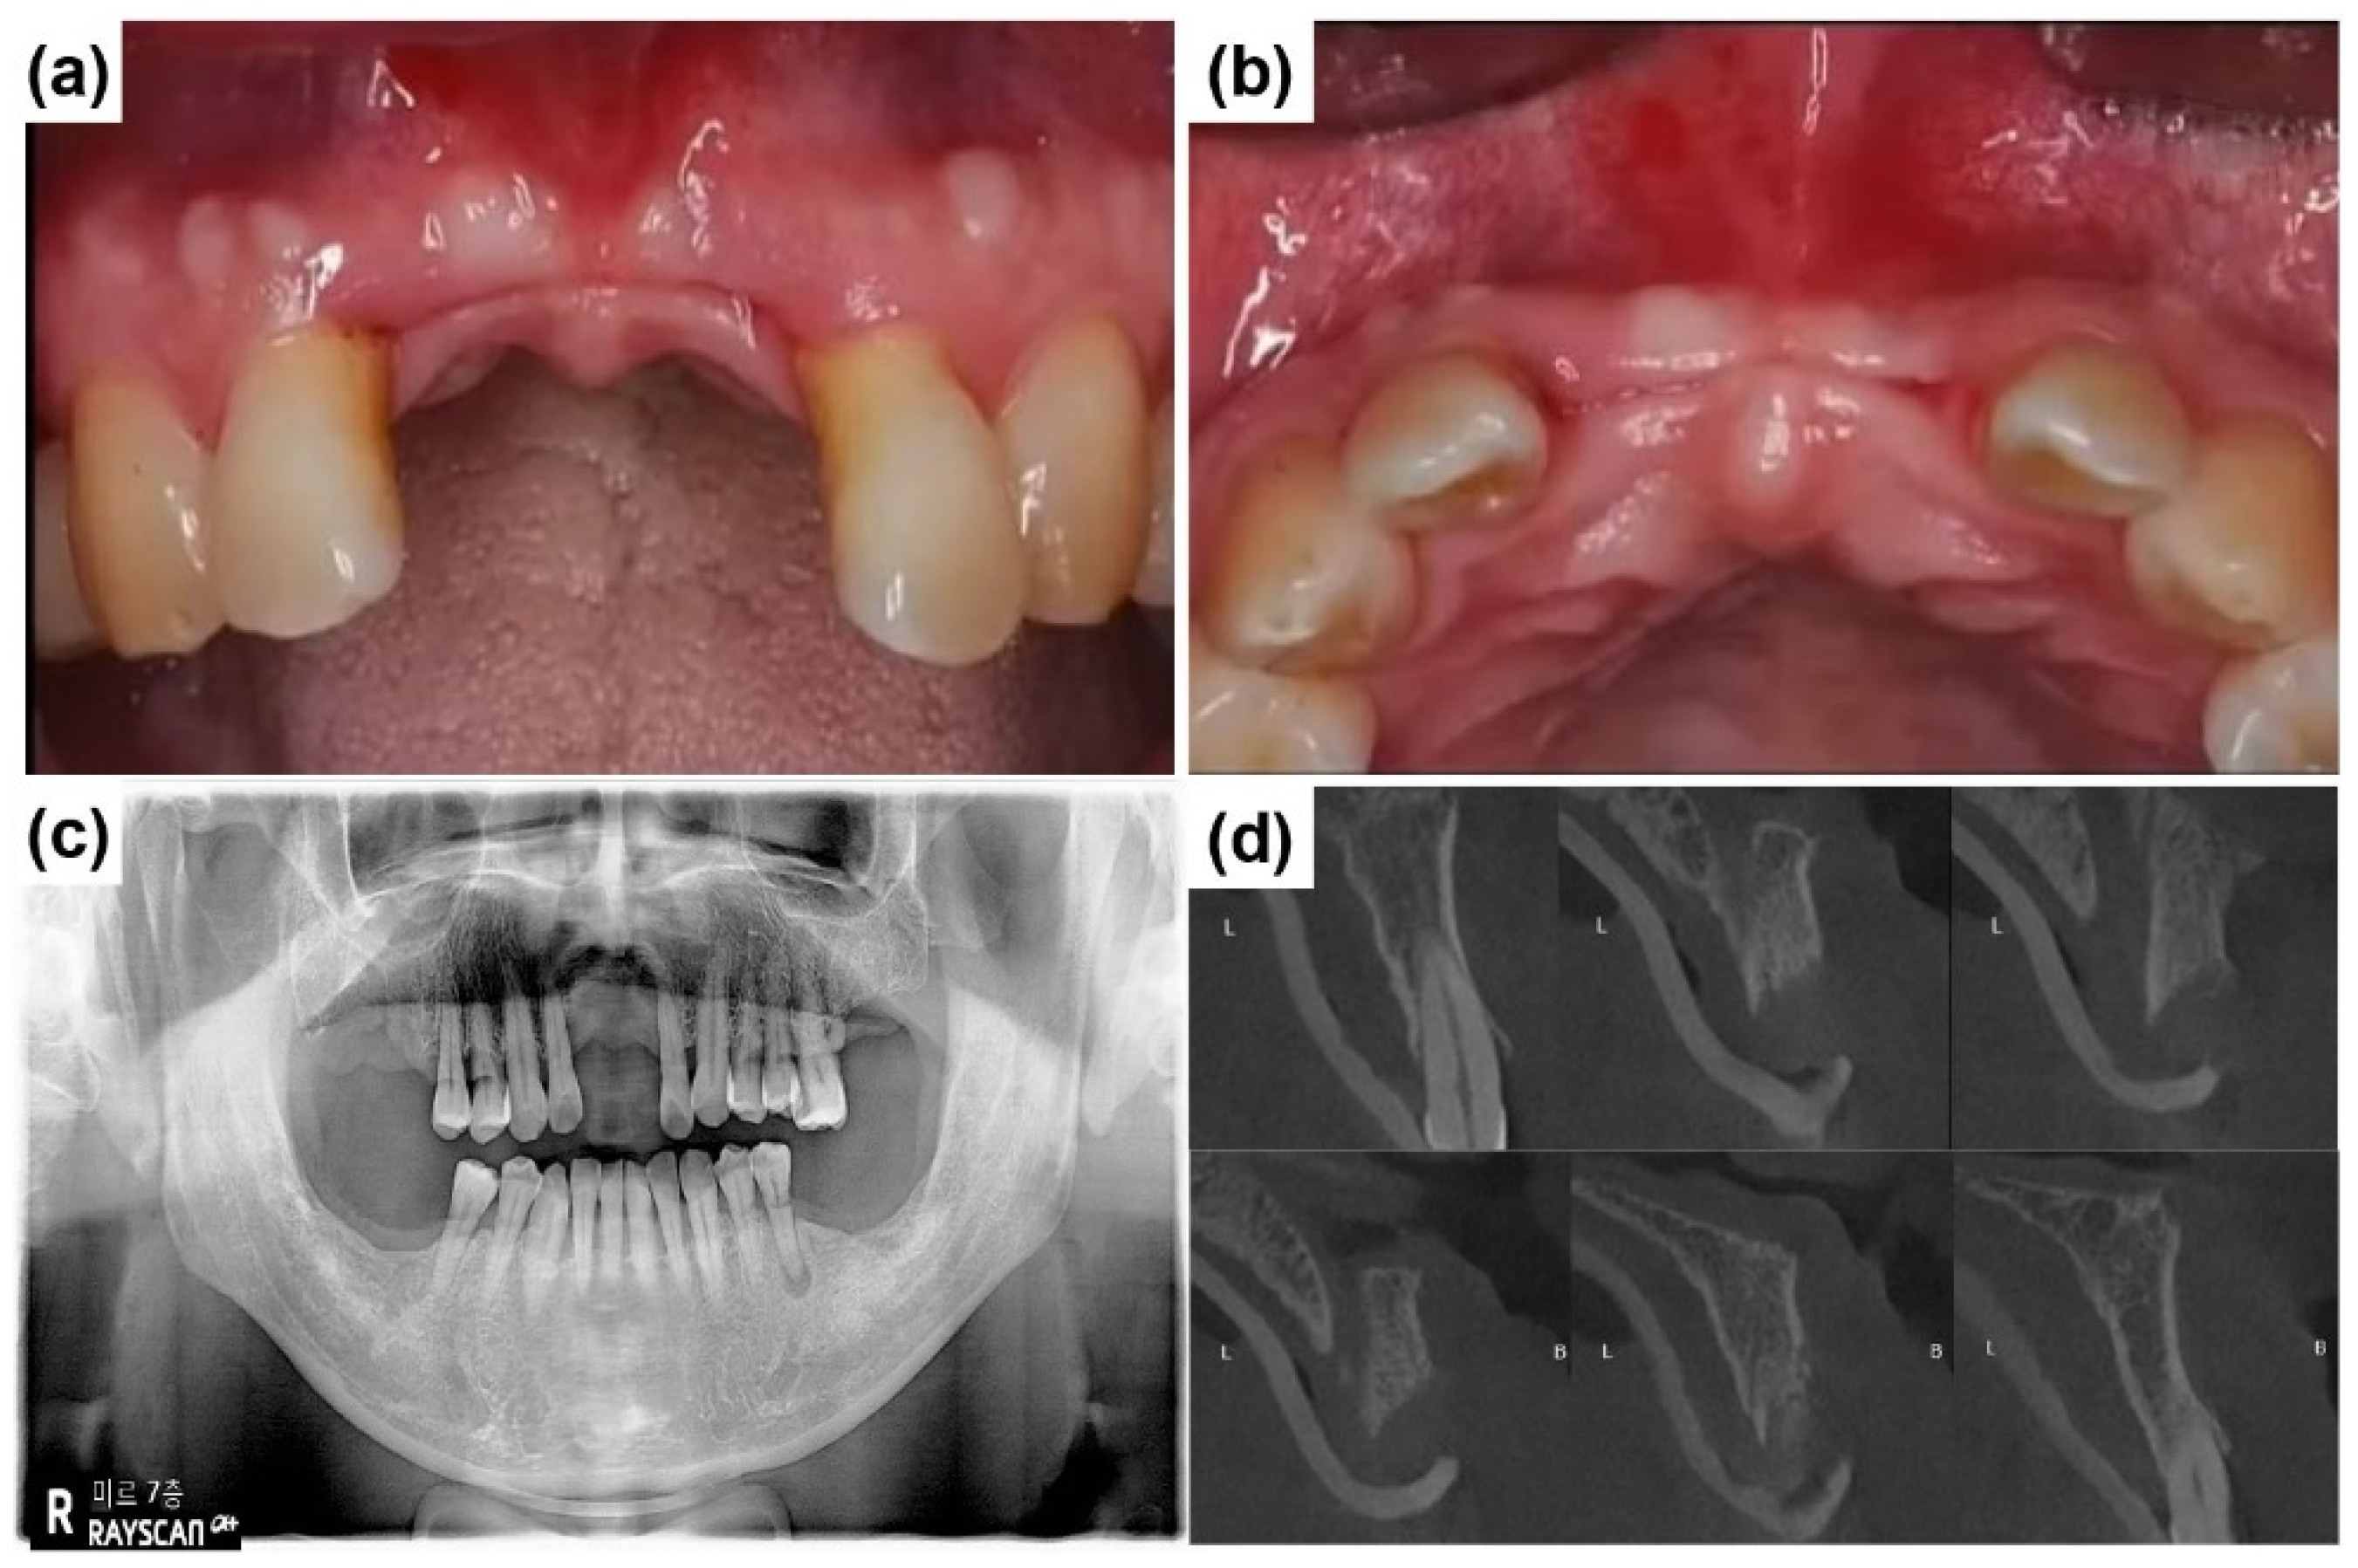

2.2. Case Report 2